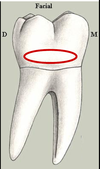

Crown Dimensions

- The mesiodistal

crown width is

greater than the

buccolingual

width. - The average

difference is

as great as 1.2

millimeters and

as small as 0.5

millimeter. - The mandibular

first molar is

normally the

largest tooth

in the arch.

Buccolingual crown width

- The greatest

buccolingual

width is at the

distobuccal cusp.

Crown outline

- The outline has

traditionally been

described as

pentagonal. - The outline

has also been

described as

hexagonal. - The angles

between the buccal

surface and the

proximal surfaces

are about equally

acute and the

lingual angles

are obtuse.

Buccal surface visibility

- More of the buccal

surface is visible

than the lingual

surface. - At least two-thirds

of the buccal

surface is visible

but only the

occlusal third of

the lingual surface

due to the lingual

tilt of the crown.

Lingual crown convergence

- The crown tapers

lingually, thereby

having a narrower

mesiodistal width

on the lingual

surface.

Distal crown convergence

- The crown

tapers distally,

thereby producing

a narrower buccolingual

width on

the distal aspect

of the crown.